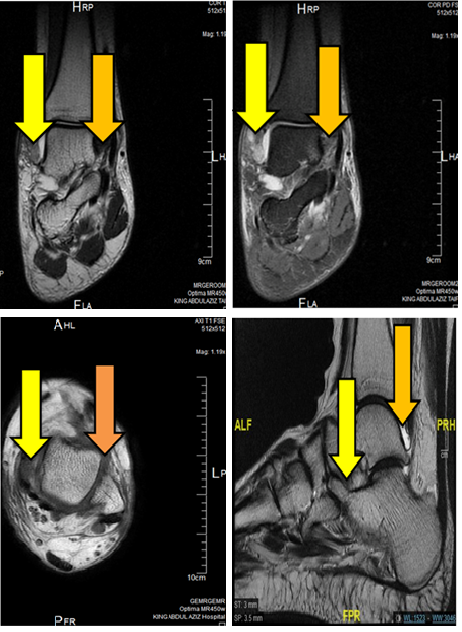

Study of Traumatic Ankle Injuries in Taif, Saudi Arabia, Using Magnetic Resonance Imaging

Samih Kajoak

International Journal of Innovative Research in Medical Science·December 1, 2022